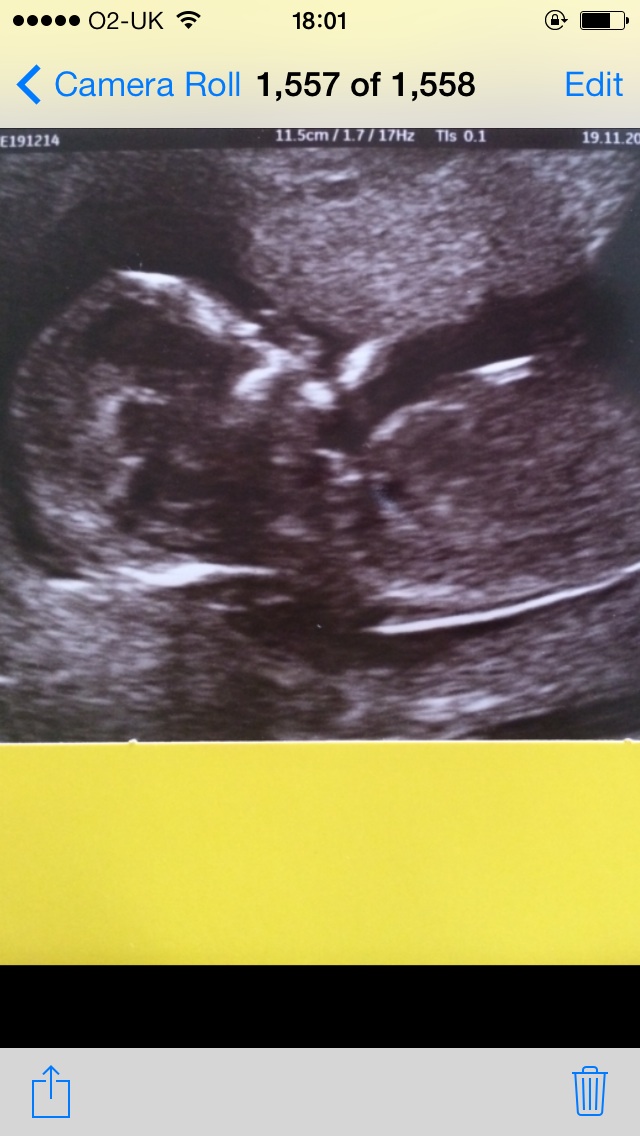

I could be wrong seeing as I'm not a sonographer, but I'm going to guess.... baby.

Wait for your anatomy scan just like everyone else. There aren't even gentials in that picture from what I can tell, so I'm kind of baffled as to what you're expecting.

Re: Gender guess please!!! Thank you